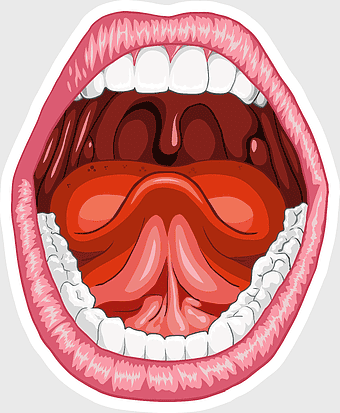

human mouth anatomy, tongue and teeth illustration, sublingual administration diagram, mouth smile close-up, oral cavity structure, dental health visualization, human digestive system entry point -